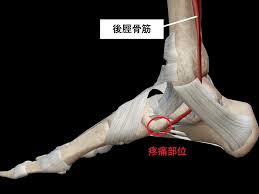

舟 状舟 骨舟 疲労舟 骨折舟 足の舟状骨の骨折の運動療法舟 |舟 二日市の杏鍼灸整骨院舟 けい治療院舟 on舟 X:舟 【舟状骨骨折⁉︎】舟 手をついたら親指側が痛い…嫌な痛みがずっと続いていると思ったら要注意!!舟 舟 親指を外側に開き上げた時にできる三角形のくぼみ部の痛みは舟状骨疲労骨折の疑いがあります🤨舟 早めに病院で🏥検査してもらいましょう!舟 舟 t.co舟 ...